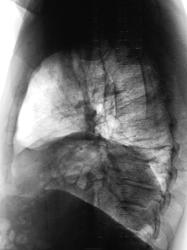

Может быть , что картина обусловлена высоким расположением левого купола диафрагмы?

Грыжа похоже, оттесняющая средостение вправо

А почему не релаксация диафрагмы, а именно грыжа? И какая грыжа имеется в виду?

Каюсь, грыжи нет. Релаксация левого купола диафрагмы. И, как сказал А.С., содержимое живота вознеслось вверх.

Такая картинка имеет место быть только последние три года, раньше все было нормально.

Просьба к вам- уточнить у пациента, что же было с ним 3 года тому назад-автоавария? ранение?

"Пытал" с пристрастием, ничего не помнит, хотя всю жизнь тяжело работал.